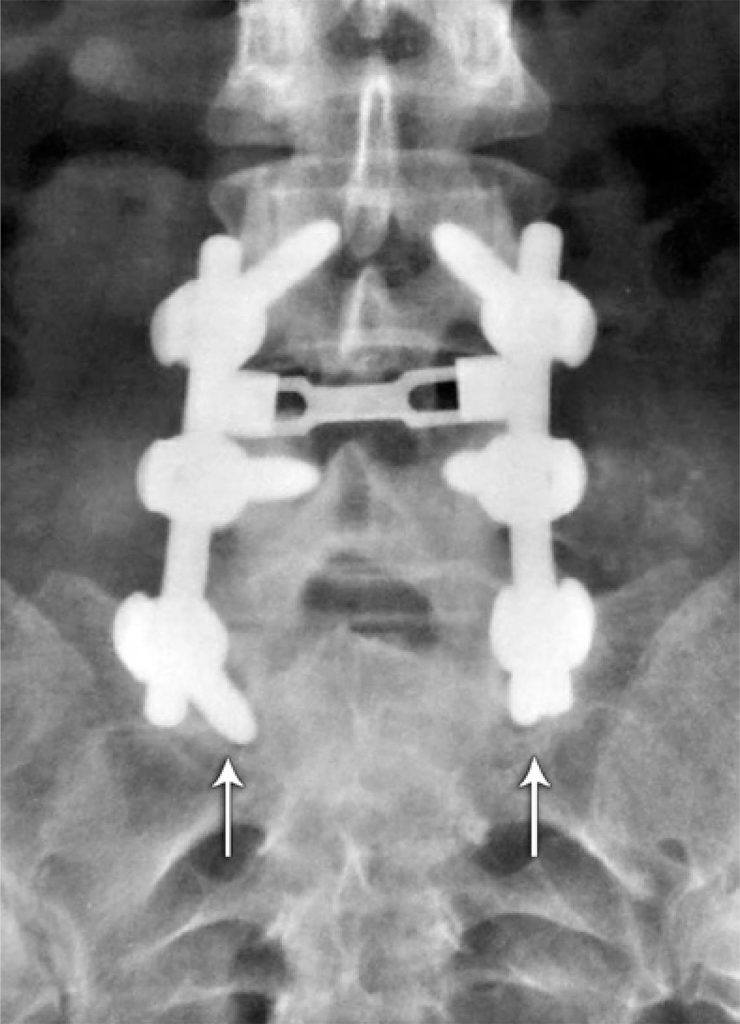

Reliability analysis of radiographic methods for determination of posterolateral lumbossacral fusion

To analyze intra and interobserver agreement of two radiographic methods for evaluation of posterolateral lumbar arthrodesis.

Twenty patients undergoing instrumented posterolateral fusion were evaluated by anteroposterior and dynamic lateral radiographs in maximal flexion and extension. The images were evaluated initially by 6 orthopedic surgeons, and after 8 weeks, reassessed by 4 of them, totaling 400 radiographic measurements. Intra and interobserver reliability were analyzed using the Kappa coefficient and Landis and Koch criteria.

Intra and interobserver agreement regarding anteroposterior radiographs were, respectively, 76 and 63%. On lateral views, these values were 78 and 84%, respectively. However, the Kappa analysis showed poor intra and interobserver agreement in most cases, regardless of the radiographic method used.

There was poor intra and interobserver agreement in the evaluation of lumbosacral fusion by plain film in anteroposterior and dynamic lateral views, with no statistical superiority between the methods.